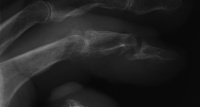

| Left index distal

interphalangeal joint tophus with thin overlying skin and nail

deformity. |

| Despite extensive

remodelling, the joint had 50 degrees of active motion. |